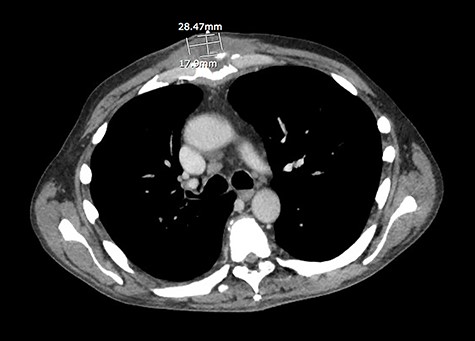

A 59-year-old male with history of metastatic prostate cancer who was undergoing chemotherapy via right subclavian port-a-cath developed catheter-associated infection with erosion of catheter through the skin. The catheter was removed and the wound left open to allow healing by secondary intention. The patient did well initially; however, 6 weeks later, he developed fullness and pain worsened with movement over the area of sterno-manubrial joint, which prompted further evaluation. Upon presentation, patient was afebrile and hemodynamically stable. Patient had leukocyte count of 7260/mm [3]. Patient was found to have a warm, dry, 3.5 cm area of fluctuance and mild overlying erythema at sterno-manubrial joint, with minimal tenderness to palpation. Computed tomography scan of chest showed 1.8 × 2.8 × 3.6 cm fluid at right subpectoral space and sterno-manubrial joint (Fig. 1). Given the seemingly small size of the abscess, medicine service pursued conservative management with empiric intravenous vancomycin initially, which was later de-escalated to intravenous cefazolin after abscess aspirate culture grew methicillin-sensitive Staphylococcus aureus. After 5 days, however, there was no sign of resolution of the sterno-manubrial fluctuance. The thoracic surgery service was consulted, whose initial impression was that the recent catheter-associated infection had tracked from the old port pocket to the cartilage between the sternum and the rib, causing significant destruction of cartilage and subcutaneous abscess formation. Patient was taken to operating room for incision, drainage and debridement of the right subpectoral space and sterno-manubrial joint abscess (Fig. 2). Patient underwent three additional serial debridements and wound wash-outs every other day. During each debridement, the wound was generously debrided using curette and low-setting cautery with excision of portion of subpectoral fascia and portion of cartilage from sterno-manubrial joint space. Bony structures remain grossly intact with no sterno-manubrial joint instability. The abscess cavity was copiously irrigated and packed with silver sulfadiazine-impregnated half-inch packing gauze. Intraoperative culture grew S. aureus that was resistant only to penicillin. Histopathology study from intraoperative samples showed tissue necrosis with accompanying marked acute inflammation, abscess formation and small fragments of benign bone. In his fourth serial debridement operation, there was adequate healthy granulation tissue present at which point wound closure was performed and a Jackson Pratt drain was placed. Patient was discharged home with additional 8 weeks of intravenous cefazolin treatment. At follow-up in thoracic surgery clinic 2 weeks later, patient’s incision had healed well with no signs of residual infection. Jackson Pratt drain was removed.

CT scan of the chest revealed a 1.8 × 2.8 × 3.6 cm fluid at right subpectoral space and sterno-manubrial joint.